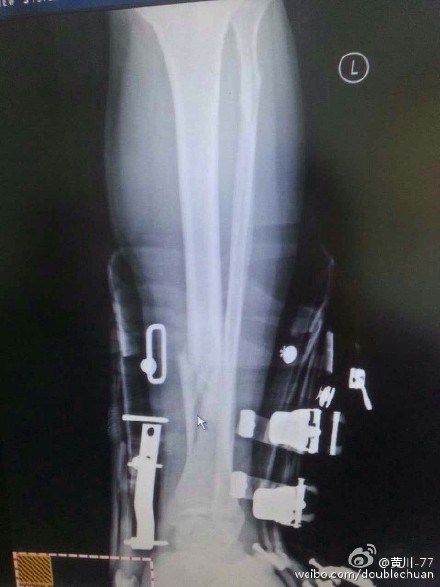

????2014年12月18日,國(guó)家一級(jí)裁判黃川(黃川-77)微博爆料:“央視名嘴韓喬生今天上午在崇禮云頂滑雪場(chǎng)玩雪地自行車(chē)撞上一位正在滑雪的美女,因?yàn)槊琅碜o(hù)甲裝備齊全,并無(wú)大礙,韓老師則小腿兩處骨折,傷勢(shì)較嚴(yán)重。骨折處在雪鞋內(nèi)部,現(xiàn)在如何脫掉硬雪鞋成為難題。”

????韓喬生在接受記者電話(huà)采訪時(shí)表示,他是參加一個(gè)助力申奧活動(dòng)時(shí)受的傷,事故發(fā)生后,立即被送往北京市的醫(yī)院進(jìn)行治療處理。